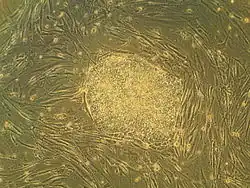

Эмбриональные стволовые клетки (ЭСК) — тип плюрипотентных клеток млекопитающих, поддерживаемых в культуре, которые получают из внутренней клеточной массы бластоцисты на ранней стадии развития эмбриона[1]. Эмбрион человека достигает стадии бластоцисты спустя 5-6 дней после оплодотворения, внутренняя клеточная масса бластоцисты человека состоит из 50-150 клеток.

Эмбриональные стволовые клетки являются плюрипотентными. Это означает, что они могут дифференцироваться во все три первичных зародышевых листка: эктодерму, энтодерму и мезодерму. Плюрипотентные клетки способны к дифференцировке во все типы клеток взрослого организма, которых насчитывается около 220. Свойство плюрипотентности отличает эмбриональные стволовые клетки от мультипотентных клеток, которые могут дать начало лишь ограниченному количеству типов клеток. В отсутствие стимулов к дифференцировке in vitro эмбриональные стволовые клетки могут поддерживать плюрипотентность в течение многих клеточных делений. Это свойство называется способность к самообновлению (англ. self-renewal). Наличие плюрипотентных клеток у взрослого организма остаётся объектом научных дискуссий, хотя исследования показали, что существует возможность получения плюрипотентных клеток из фибробластов взрослого человека в лабораторных условиях в процессе так называемого репрограммирования клеток[2].

Эмбриональные стволовые клетки выделили из мышиных эмбрионов в 1981 году Мартин Эванс и Мэтью Кауфман, а также независимо от них Гэйл Мартин[4][5]. Прорыв в исследовании эмбриональных стволовых клеток человека произошёл в ноябре 1998 года в группе Джеймса Томсона в Университете Висконсина. Учёные выделили такие клетки из бластоцисты человека[6].